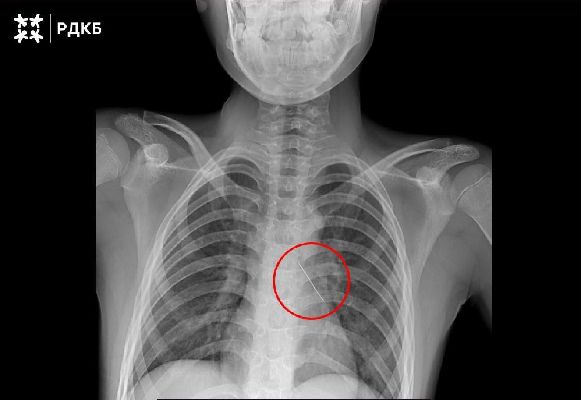

При поступлении подросток говорил только шёпотом и жаловался на сильную боль в груди. Рентгеновское исследование выявило инородное тело в нижней доле левого бронха. Вокруг булавки скапливалась мокрота, а острый конец повредил стенку бронха. Врачи опасались коллапса лёгкого.

Специалисты отделения реконструктивной хирургии провели малоинвазивное вмешательство. Через эндоскоп они удалили слизь, обнаружили колпачок французской булавки и оптическими щипцами извлекли предмет. Кровотечение оказалось минимальным и остановилось самостоятельно. Через три дня ребёнка выписали, врачи продолжат наблюдение по месту жительства.